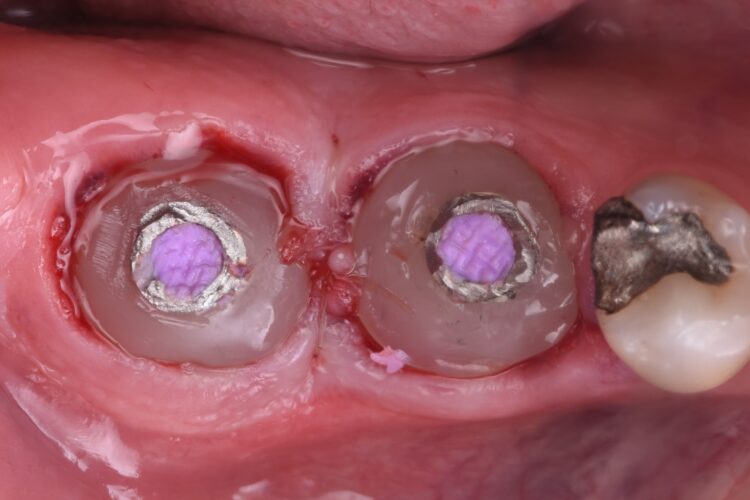

Dental implants were then placed using the sleeveless surgical guides. The guided kit from CONELOG® is fantastic, as the screw-in carriers allow for very accurate positioning. After verifying the implant placement, the carriers are replaced and can be used to maintain patency of the implant opening while the graft material is packed into the site.

MinerOss® Putty allograft (BioHorizons Camlog) is routinely selected for these cases. The handling properties are exceptional, making placement easy. Additionally, due to its 10% collagen composition, integration is exceptional, avoiding the ‘popcorn’ effect seen with other materials. The graft material was packed to the bone level, again to reduce the build-up of graft material in the soft tissue.

For this case, 5.0 mm x 9.0 mm CONELOG® Progressive-Line implants were utilised, which is a highly favourable system for immediate placement. The design features that make it particularly effective include:

• Aggressive thread design for high primary stability.

• Promote® (sand blasted, acid etched) surface treatment, promoting rapid osseointegration.

• Grade 4 titanium, commercially pure titanium offering predictable integration.

Custom healing abutments were constructed using a temporary abutment and composite, polished to a high lustre using silicone wheels. The patient was given standard post-operative instructions to support healing of the surgical site in the months to come.